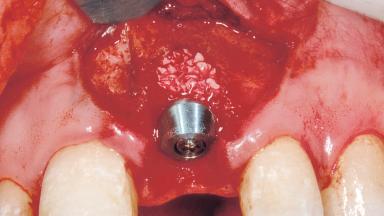

Immediate Placement of an Implant in a Maxillary Left Central Incisor Site

A 33-year-old female patient presented with an upper left central incisor that required extraction after a failed endodontic therapy. The tooth had been traumatized when the patient was a teenager and had undergone several endodontic treatments, including two apicectomy procedures. The patient was in good health and did not smoke. Clinical examination showed that the patient had a high lip line. In full smile, the gingival margins of the upper teeth were visible to the first molars. The gingival margins of central incisors 11 and 21 were only just showing. Examination of tooth 21 confirmed that the tooth was mobile and had hypererupted by 1 mm.

Bone Augmentation Horizontal|Simultaneous

Augmentation Materials Xenogenous|Membrane

Placement Protocol Immediate implant placement

Socket Integrity Damage to one or more bone walls

Bone Volume Damage to one or more socket walls